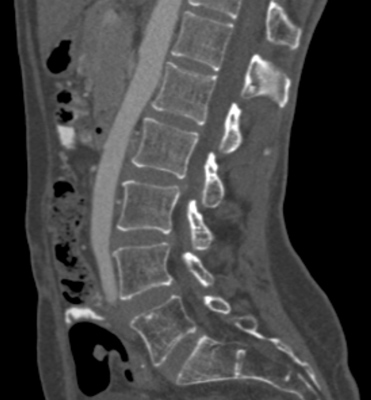

We trained and evaluated the method with five sets of CT and MR scans that visualize the spine. Reference segmentation masks for four of these datasets are publicly available, which allowed for a comparison with other publications that used the same data. Examples of images from the datasets are shown in Figure 3.

The thoracolumbar spine CT dataset consists of 15 dedicated spine CT scans that visualize all thoracic and lumbar vertebrae. It was originally used for the spine segmentation challenge held in conjunction with the Computational Spine Imaging (CSI) workshop at MICCAI 2014 (Yao et al., 2016). All subjects were young adults ( years) without vertebral fractures who were scanned with IV-contrast administration. The scans were reconstructed to in-plane resolutions of and slice thicknesses of . Semi-automatically obtained reference segmentations were provided by the challenge organizers. To allow for a comparison with the challenge results, we used the same data split with 5 scans for evaluation and the remaining 10 scans for training and development.

The xVertSeg.v1 dataset consists of 15 lumbar spine CT scans of subjects with compression fractures of various grades and types (Ibragimov et al., 2017). Manual reference segmentations are available for the lumbar vertebrae and were defined through a consensus reading of two observers. The scans were reconstructed to in-plane resolutions of and slice thicknesses of . There are currently two other publications that used the same dataset, but with different evaluation/training separation (Janssens et al., 2018; Sekuboyina et al., 2017). We therefore used the scans for evaluation and the remaining 10 scans for training.

The low-dose chest CT dataset consists of 55 scans from the National Lung Screening Trial (The National Lung Screening Trial Research Team, 2011). These scans were acquired for lung imaging and visualize in addition to the lungs a variable section of the thoracic and upper lumbar vertebrae. The scanned subjects were heavy smokers aged 50 to 74 years and therefore at increased risk for vertebral compression fractures due to their advanced age and smoking history. The scans were acquired with low radiation dose and reconstructed to in-plane resolutions of and slice thicknesses of . We created manual and semi-automatic reference segmentations for this dataset: 10 scans were used for evaluation and were therefore fully manually annotated by drawing along the contour of each vertebra in sagittal slices using an interactive live wire tool (Barrett and Mortensen, 1997). The contours were converted into segmentation masks, in which inaccuracies and other mistakes were corrected voxel-by-voxel. An additional set of 5 scans was annotated in the same way and was used to train a preliminary version of the network. This network was used to predict rough segmentations in the remaining 40 scans. These rough segmentations were manually inspected and corrected voxel-by-voxel, and were used for training of the final network. This strategy enabled us to create a large training set with substantially less manual annotation effort compared to fully manual segmentation, which is not necessarily needed for training data. Additionally, a second observer fully manually annotated two scans from the evaluation set for an estimation of the interobserver agreement. All fully manual and semi-automatic segmentations were performed in sagittal views by observers who received detailed instructions beforehand. Additionally, all segmentations were validated by an experienced radiologist.

The lumbar spine CT dataset consists of 10 scans of healthy subjects and corresponding manual reference segmentations of the lumbar vertebrae (Ibragimov et al., 2014; Korez et al., 2015). The scans were reconstructed to in-plane resolutions of and slice thicknesses of . Because this dataset is the smallest of the datasets that we included, it was used for an external evaluation of our supervised approach. Scans from this dataset were therefore only used for evaluation and were not part of the training set.

The lumbar spine MR dataset consists of 23 T2-weighted turbo spine echo MR images acquired at 1.5T in sagittal orientation (Chu et al., 2015). The scans have a resolution of . Manual reference segmentations are available for 7 vertebrae (T11-L5) in all scans. These reference segmentations contain only the vertebral bodies, not the entire vertebrae.